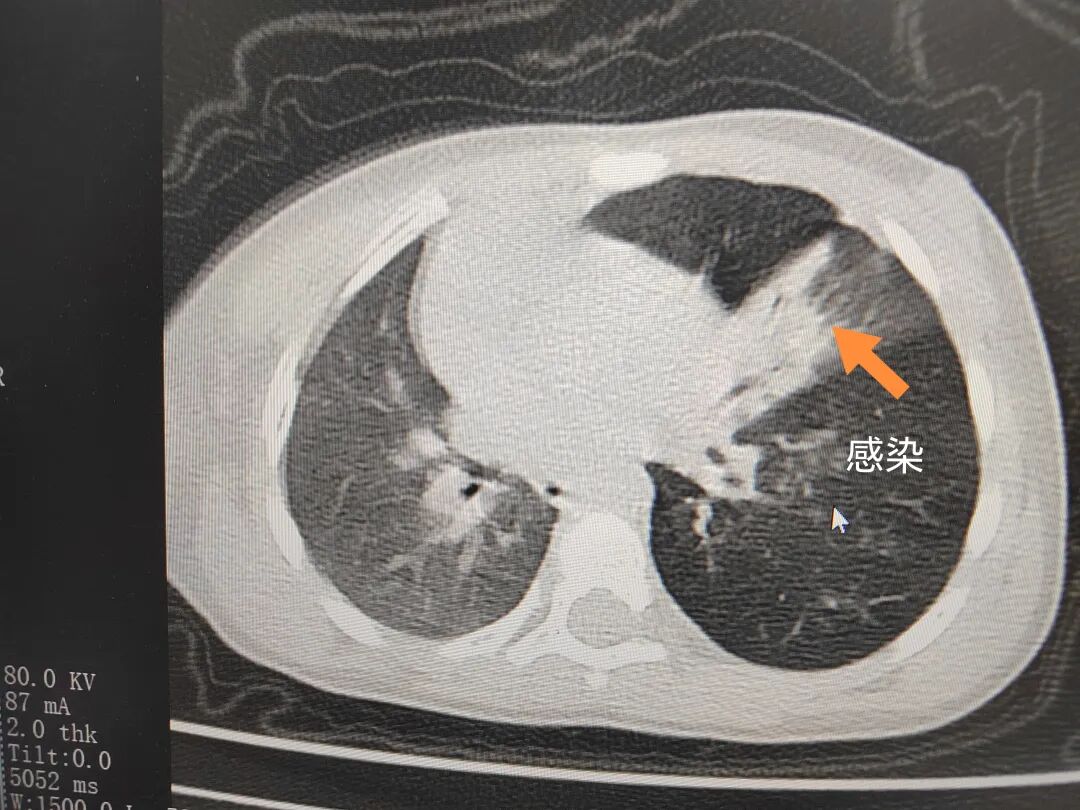

三天后(11月13日),趙寶出現高熱、咳喘加重,家長著急了,再次帶他來到醫院。CT檢查顯示左肺過度充氣,左肺上下葉支氣管主干見不規則高密度影,左肺上葉可見大片狀密度增高影,縱隔窗實變,提示為“左側支氣管內異物并繼發性改變,左肺上葉舌段肺膨脹不全”。

市二院小兒呼吸內科團隊迅速為患兒制定了周密的手術方案,并很快安排了氣管鏡探查。術中,主治醫師田慧等憑借嫻熟的氣管鏡操作技術成功將異物大塊板栗取出。由于板栗在氣管內存留時間較長,質地軟糯易碎,大大增加了手術難度。檢查還發現,異物停留部位的氣管黏膜已出現充血紅腫、糜爛,導致患兒住院時間相應延長。此次事件給趙寶的家庭帶來了不小的驚嚇與擔憂,也再次為廣大家長敲響了警鐘。